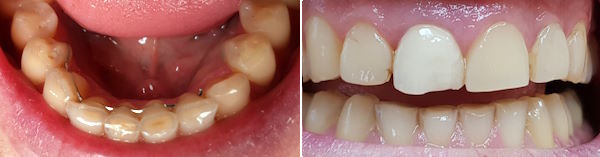

71-jährige Patientin (03.02.2026 / 137)

Keilförmige Defekte sind die häufigsten Zeichen von Bruxismus und wie ein kleiner Spiegel der Seele.

Mit kleinen Retentionsgrübchen kann man das Komposit besser retinieren. Der Bruxismus bewirkt in vielen Fällen nach 10-20 Jahren einen zweiten keilförmigen Zahnhalsdefekt unter der Zahnhalsfülung.

74-jährige Patientin (03.10.2024 / 7938)